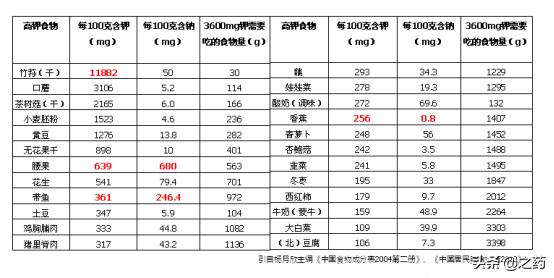

Panther en a inclus un pour vousListe des aliments riches en potassiumCe tableau est tiré des directives diététiques chinoises 2010 et il est recommandé de le conserver.

solSelon les directives diététiques chinoises pour les résidents, nous devrions consommer au moins 2 000 mg de potassium par jour.Dans notre alimentation quotidienne, en effet, de nombreux aliments sont riches en potassium, compléter ce besoin quotidien n'est pas difficile, alors quels sont les aliments riches en potassium ? Monsieur vous les présente brièvement.

●légumineusesC'est une excellente source de potassium. Parmi les produits à base de soja, non seulement ils sont riches en potassium, mais ils sont également relativement riches en fibres alimentaires, avec environ 130 grammes de haricots blancs et peuvent apporter421 mg de potassiumLes lentilles sont également une bonne source de potassium.

●Pommes de terre et arachides. Six taels de pommes de terre fournissent1600 mgde potassium, une demi-livre d'arachides apporte1100 mgLe potassium, en plus des deux ingrédients, est tout aussi riche en fibres alimentaires, et une augmentation adéquate de la consommation de pommes de terre est également très importante pour maintenir la santé du tractus intestinal.

●Épinards, betteraves. Cent grammes de betterave rouge contiennent encore environTrois cents milligrammes de potassium.Les épinards sont également riches en potassium, en vitamine A, en vitamine K et en calcium. Leur teneur en calcium est relativement élevée, mais il est recommandé de les faire blanchir lorsqu'on les cuisine, car leur teneur en acide oxalique est relativement élevée.

●Tachanoko, jus d'orange. Une tasse d'environ une demi-livre de jus d'orange fournira près de500 mg de potassium.Les agrumes sont également riches en vitamine C, qui joue également un rôle important dans notre organisme, mais le Dr Xie vous conseille de ne pas consommer beaucoup de jus d'orange si vous avez un taux d'acide urique élevé, car vous risquez d'augmenter encore votre taux d'acide urique, surtout à long terme.

●bananesRiche en potassium, comme vous le savez certainement tous, une banane mûre contient près de 450 mg de potassium, mais si vous souffrez de diabète, ce n'est pas une bonne idée d'abuser des bananes en raison de leur teneur élevée en sucre.